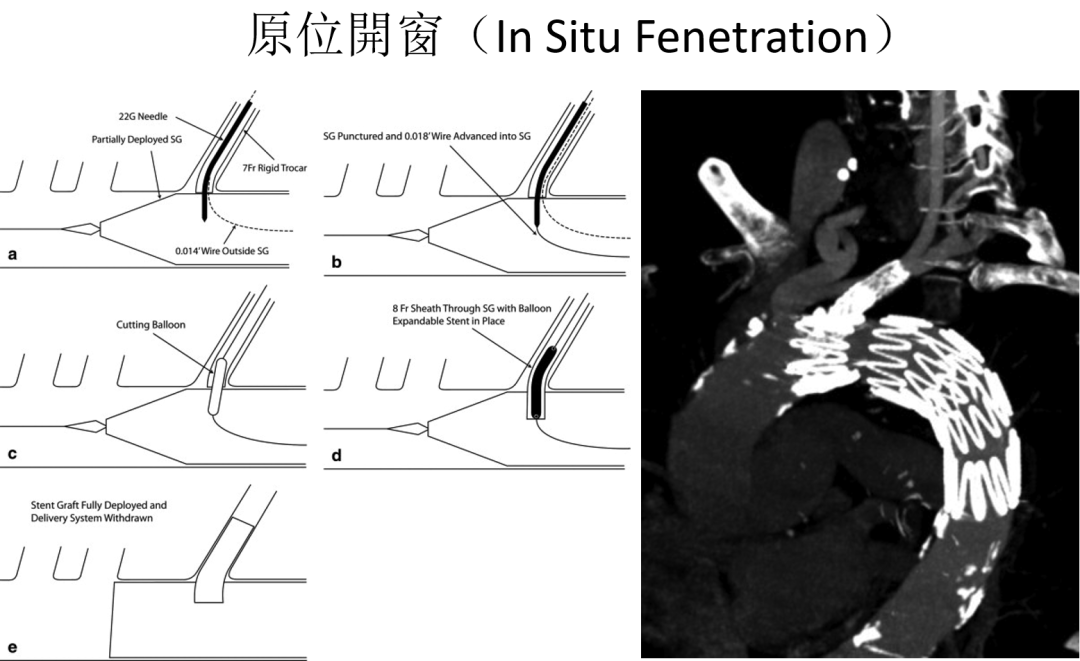

腔内技术的“野路子”

随着腔内技术的发展,烟囱(Chimney)技术和术中开窗(On-Table Fenestration)曾一度流行。然而,这些技术往往伴随着较高的内漏(Endoleak)发生率和支架闭塞风险,且操作复杂,极度依赖术者的经验。

客制化与“现成型”的博弈

Zenith分支支架虽然早年问世,但其“客制化(Custom-Made)”的属性导致等待时间长(数周甚至数月),对于急性病变患者往往望尘莫及。

破局利器

TBE支架的设计哲学与操作精髓

TBE支架的出现,解决了“等待时间”与“解剖适应”之间的矛盾。